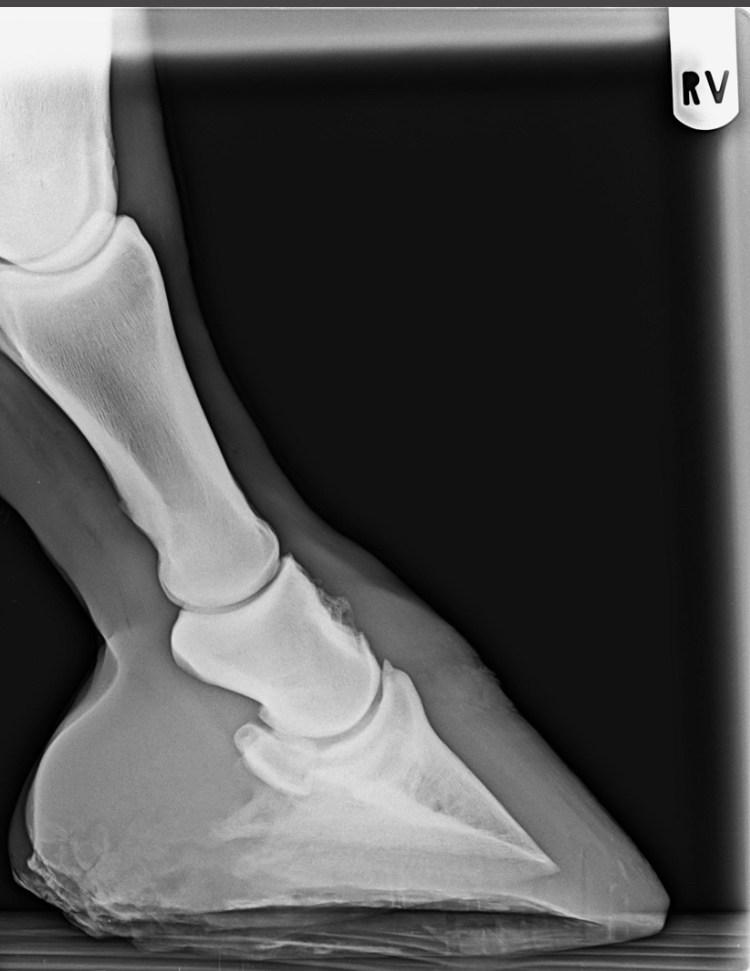

Orthopädie

Bildgebende Verfahren:

Ultraschall, Röntgen, JETZT auch Endoskopie